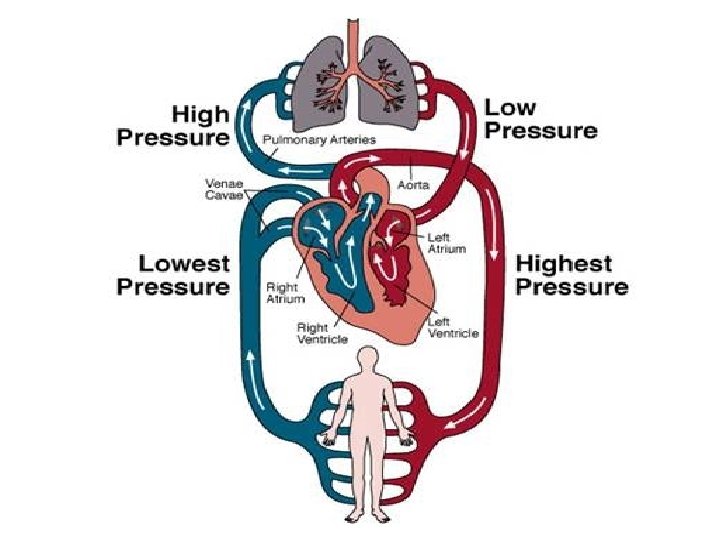

Circulation Summary • Consists of heart, blood and blood vessels • Double-circulation as blood travels twice through heart in one journey • Pulmonary circulation (heart lungs) • Systemic circulation (Heart body) • Oxygenated (O 2 rich) heart to body • Deoxygenated (O 2 poor) body to heart

Path of Oxygenated Blood • Pulmonary vein left atrium • Through mitral valve down into the left ventricle. • The ventricle then contracts forcing the mitral valve closed and opening the semilunar valve. • The blood then flows up into the aorta and around the body.

Path of Deoxygenated blood • Vena cava right atrium • Through tricuspid valve right ventricle. • Ventricle contracts, tricuspid valve closes, semilunar valve opens. • Blood flows to the pulmonary artery lungs.